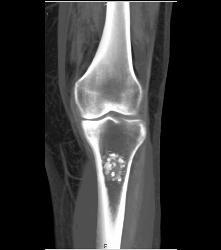

Osteochondroma